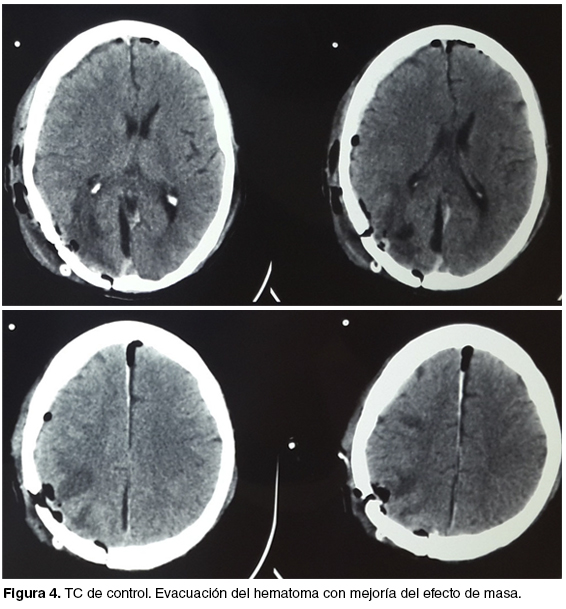

La TC de control muestra una evacuación completa con franca mejoría del efecto de masa (figura 4). La evolución ulterior fue favorable; lográndose desvincular al paciente de la asistencia ventilatoria a las 48 horas, pasando luego a sala general donde se mantiene lúcido y sin déficit focal neurológico. La anatomía patológica confirma metástasis de primitivo renal y se vincula al paciente con oncólogo para continuar el tratamiento de su enfermedad neoplásica.